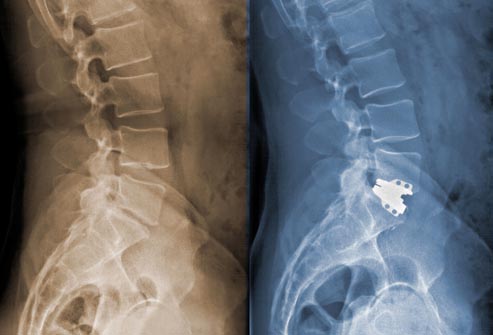

Surgery

If long-lasting back pain is interfering with your daily life, and other treatments have not provided relief, you may be a candidate for surgery. Depending on the cause of your pain, a surgeon may remove a herniated disc, widen the space around the spinal cord, and/or fuse two spinal vertebrae together.

Diagnosing Low Back Pain